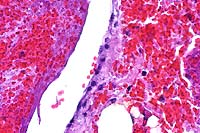

20x

obj

- Case 7-1. Subcutis, skeletal muscle. Several

vessels are occluded by fibrinocellular thrombi and the vessel

walls are disrupted by neutrophils and macrophages. Some skeletal

muscle fibers have hyaline degeneration and fragmentation.

AFIP Diagnoses:

- 1. Haired skin, dermis and subcutis: Thrombosis, fibrinoid

necrosis, and acute vasculitis, multifocal, moderate, with diffuse

hemorrhage, mixed breed, porcine.

2. Skeletal muscle: Thrombosis, fibrinoid necrosis, and acute

vasculitis, multifocal, moderate, with interstitial edema and

myodegeneration.